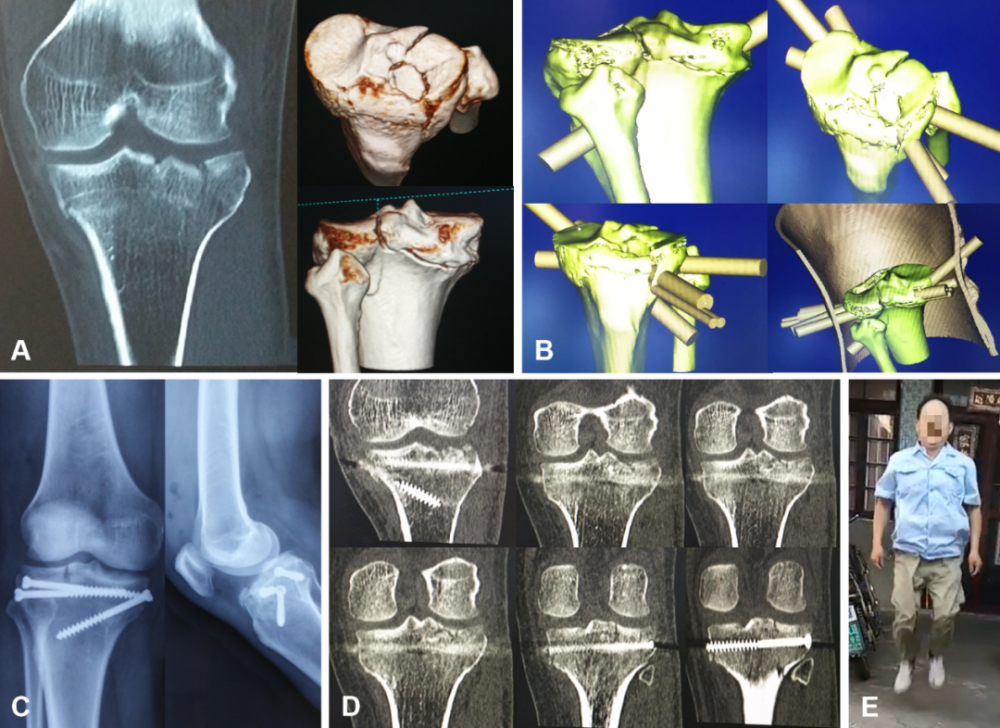

胫骨平台粉碎性骨折并塌陷通常需做较大切口直视下复位并用大块钢板固定,损伤较大,血运破坏较多,感染机会亦随之增多。作者利用3D打印技术,一改常规切开复位钢板内固定术式,针对设计了经皮3D打印导板,精准建立起对已塌陷胫骨外侧平台的球囊复位兼植骨通道,规划并精准建立了全部螺钉的固定通道,仅用5个长仅半厘米左右的切口就又快又好地完成了取骨、复位、植骨和3枚螺钉内固定等操作,为患膝快速而完全康复打下了基础(图2)。

图2 男,44岁,右胫骨平台粉碎性骨折 (A) CT示右胫骨内、外侧平台骨折、外侧平台塌陷;(B) 设计具有胫骨平台塌陷骨块之球囊复位与植骨通道和3枚固定螺钉通道的经皮导板;(C) 术后复查膝关节正侧位X线片示骨折复位,螺钉固定恰当;(D) 术后复查CT示骨折复位,关节面平整,螺钉固定恰当;(E) 术后2年弹跳自如。